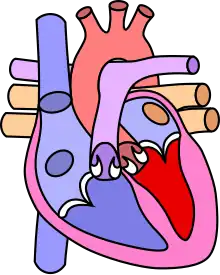

![]() | |

| Diagram of a healthy heart and one with tetralogy of Fallot | |

Tetralogy of Fallot (TOF), formerly known as Steno-Fallot tetralogy,[9] is a congenital heart defect characterized by four specific cardiac defects.[4] Classically, the four defects are:[4]

- Pulmonary stenosis, which is narrowing of the exit from the right ventricle;

- A ventricular septal defect, which is a hole allowing blood to flow between the two ventricles;

- Right ventricular hypertrophy, which is thickening of the right ventricular muscle; and

- an overriding aorta, which is where the aorta expands to allow blood from both ventricles to enter.

Four malformations

"Tetralogy" denotes four parts, here implying the syndrome's four anatomic defects.[2] This is not to be confused with the similarly named teratology, a field of medicine concerned with abnormal development and congenital malformations (including tetralogy of Fallot). Below are the four heart malformations that present together in tetralogy of Fallot:

| Condition | Description |

|---|---|

| Pulmonary Infundibular Stenosis | A narrowing of the right ventricular outflow tract. It can occur at the pulmonary valve (valvular stenosis) or just below the pulmonary valve (infundibular stenosis).[4] Infundibular pulmonic stenosis is mostly caused by the overgrowth of the heart muscle wall (hypertrophy of the septoparietal trabeculae),[42] however, the events leading to the formation of the overriding aorta are also believed to be a cause. The pulmonic stenosis is the major cause of the malformations, with the other associated malformations acting as compensatory mechanisms to the pulmonic stenosis.[43] The degree of stenosis varies between individuals with TOF and is the primary determinant of symptoms and severity. This malformation is infrequently described as sub-pulmonary stenosis or subpulmonary obstruction.[44] |

| Overriding aorta | An aortic valve with biventricular connection, that is, it is situated above the ventricular septal defect and connected to both the right and the left ventricle. The degree to which the aorta is attached to the right ventricle is referred to as its degree of "override." The aortic root can be displaced toward the front (anteriorly) or directly above the septal defect, but it is always abnormally located to the right of the root of the pulmonary artery. The degree of override is extremely variable, with 5–95% of the valve being connected to the right ventricle.[42] |

| Ventricular septal defect (VSD) | A hole between the two bottom chambers (ventricles) of the heart. The defect is centered around the most superior aspect of the ventricular septum (the outlet septum), and in the majority of cases is single and large. In some cases, thickening of the septum (septal hypertrophy) can narrow the margins of the defect.[42] |

| Right ventricular hypertrophy | The right ventricle is more muscular than normal, causing a characteristic boot-shaped (coeur-en-sabot) appearance as seen by chest X-ray. Due to the misarrangement of the external ventricular septum, the right ventricular wall increases in size to deal with the increased obstruction to the right outflow tract. This feature is now generally agreed to be a secondary anomaly, as the level of hypertrophy tends to increase with age.[45] |